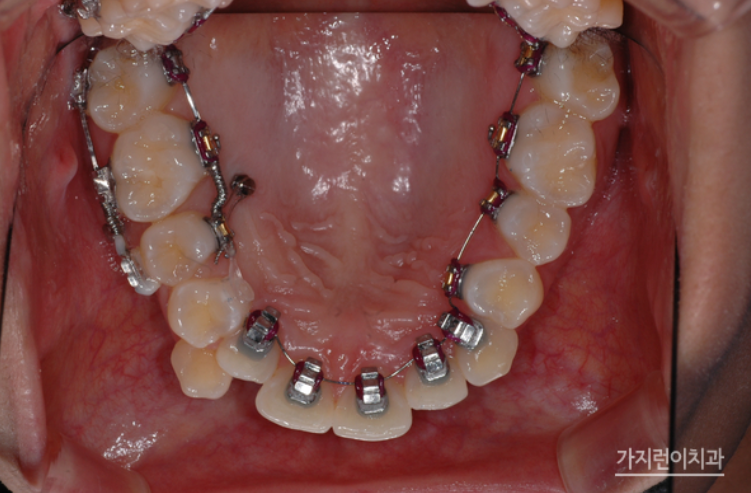

해당 환자 분은 위의 사진에서 보이는 것처럼 코와 턱끝이 잘 발달되어 있기 때문에 입술이 후방으로 들어가면 안 되는 환자였는데요. 만약 여기서 발치 교정을 했다면 환자의 입술이 과도하게 꺼질 우려가 있었습니다. 그래서 비발치교정으로 진행하게 된 건데요. 비발치 치료를 결정한 만큼 교정용 브라켓 외에도 필요한 힘을 충분히 줄 수 있도록 미니스크류를 사용했습니다. 여기에 상악은 교정장치를 치아의 뒷면에 부착하는 설측교정으로 진행하고, 하악은 일반적인 순측교정으로 진행하는 콤비교정 방식을 적용하였습니다.